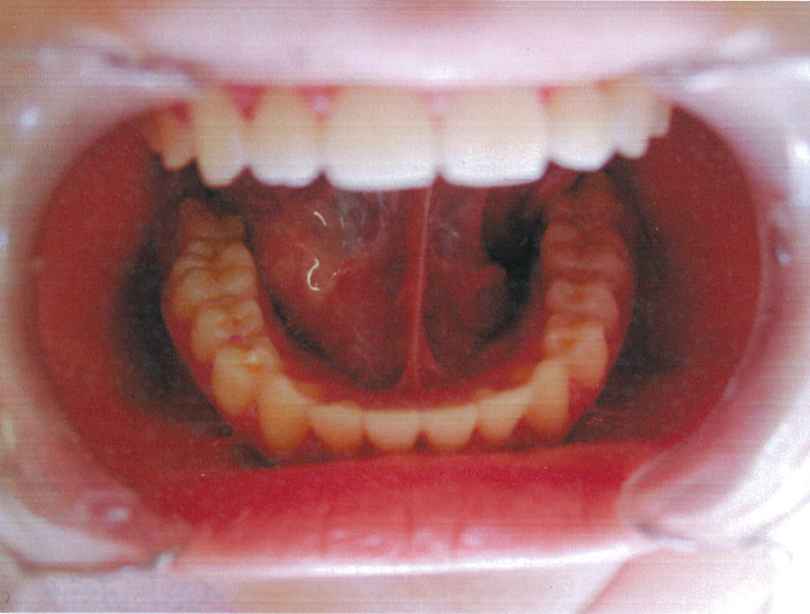

現代の子ども達は、よく調理されたやわらかいものを食べることが多く、それに伴い、あごの発達が悪くなり、歯の大きさに対して、あごの大きさが小さく、スペースがないために前歯がデコボコになったり、その後ろに生えてくる犬歯(前から3番目の歯)が生えるスペースを失い、外側に生えてしまう八重歯という歯並びになりやすいのです。

永久歯になってからでは(小学校高学年から中学校1、2年)、子ども達の成長期のピークを過ぎていることが多く、歯を抜いて矯正する頻度が増えてしまいます。

床矯正装置は、つけることによって、口の中を毎日拡大していくことができ、あごの発育を助け、永久歯が綺麗に生えるスペースを確保し、綺麗な歯並びを作ることができるようになります。また、しっかりとしたあごをつくることで、健康で充分な成長発育を促す助けとなるものと考えています。

『良い歯並び』とは、真っ直ぐに生えることの他に、生えるスペースがあるかということも大変重要です。『矯正=抜歯』のイメージがありがちですが、豊歯科で行っている矯正は、正しいあごの大きさに骨格を整える『床矯正』といい、永久歯がキレイに並ぶように土台を作ってあげることを目的としています。